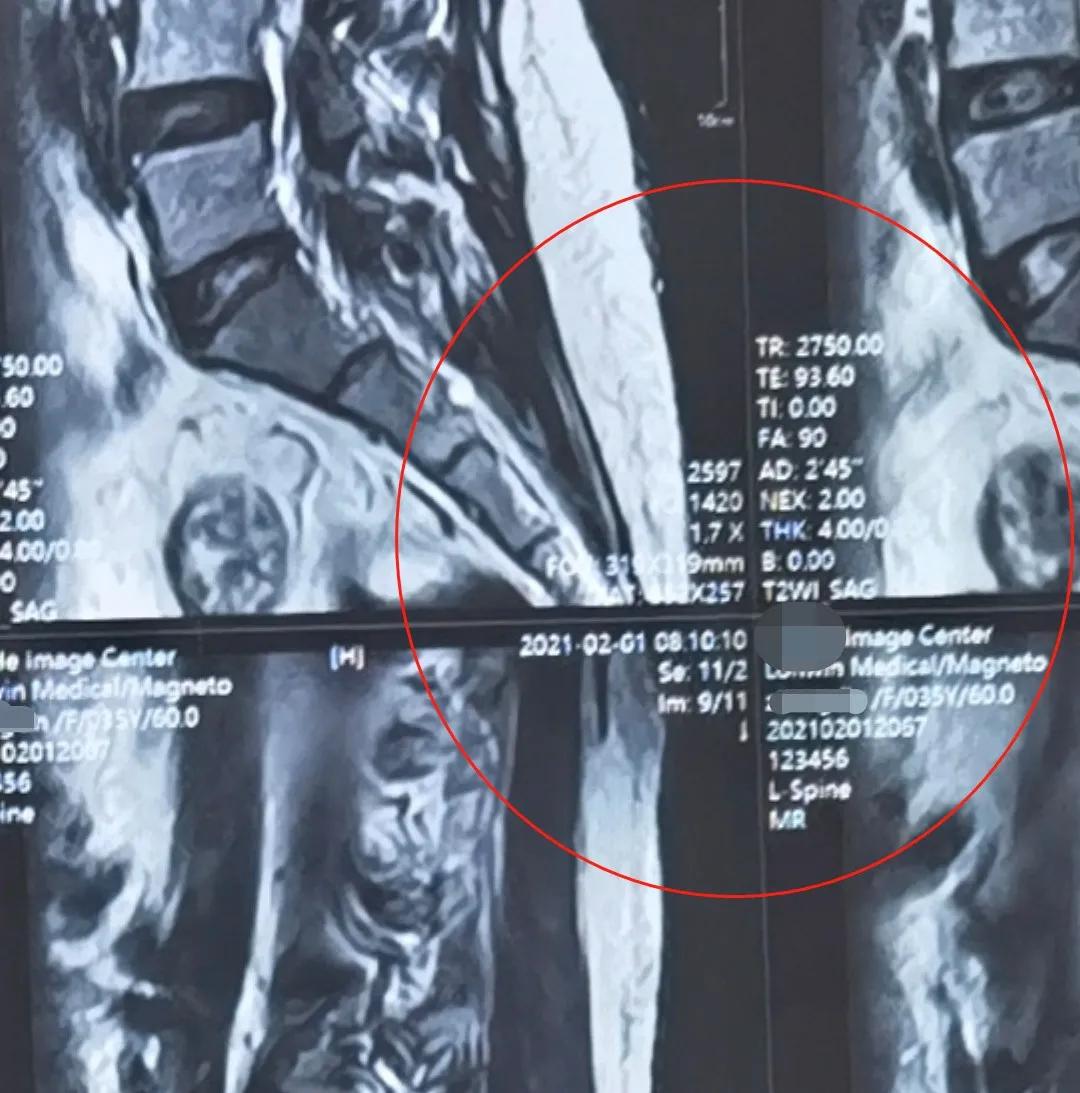

5、然后在手机上打开这张照片,两指滑动放大照片,如果片子上面的白色小字和日期显示得清清楚楚,那么这张片子的质量就非常好了。把它传给医生就能观察得非常清楚,这就是一张电子版的X光片或者是磁共振。

放大后,可以看清里面的小字